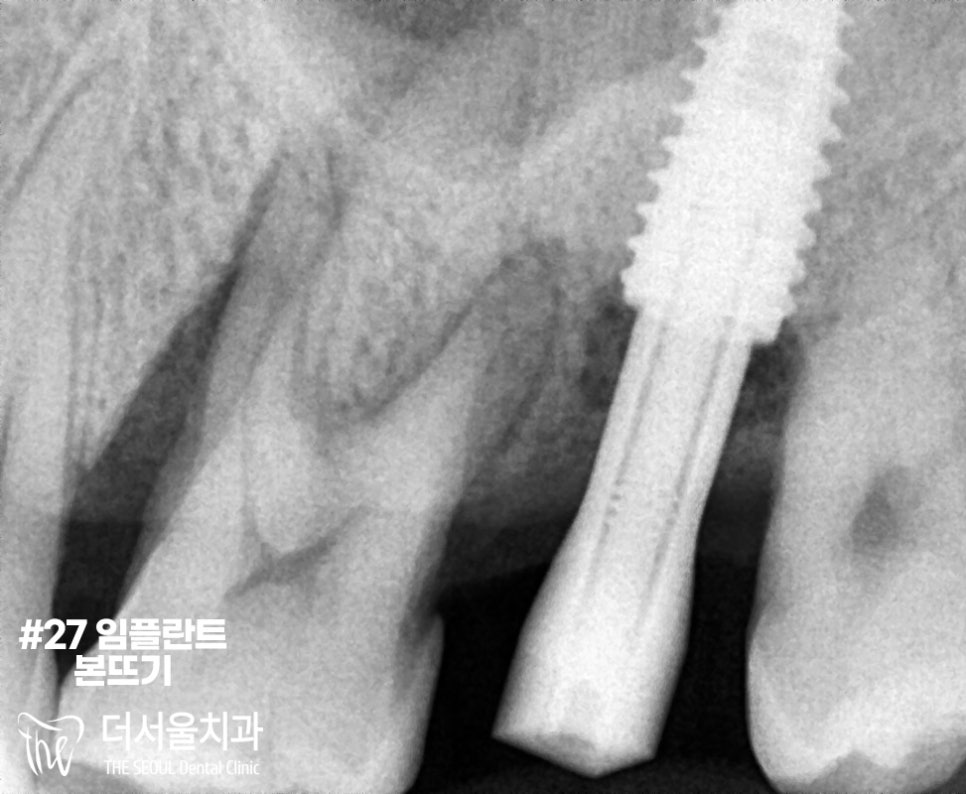

그 후, 양쪽 본을 뜨고

그대로 가셨습니다.

이후 다음 내원 때 골결합이 잘 이뤄지고

크라운 제작 완료가 이뤄졌다면,

보철 세팅으로 마무리하게 되는데요.

우선은 다음 내원 때,

보철 세팅으로 끝내는 것으로

환자분께 설명드렸습니다.